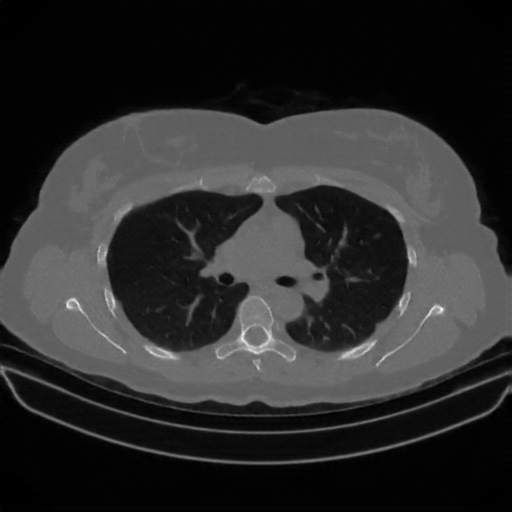

Targeted Slice 70 - Lung Window Analysis (Generated vs Real Venous)

0.763

Lung SSIM

85.0

Lung RMSE

36.7

Lung MAE

Average Lung Window Metrics Across All Slices (170 slices) - Generated vs Real Venous

0.767

Lung SSIM (Avg)

89.5

Lung RMSE (Avg)

37.4

Lung MAE (Avg)

Image Grid

4Γ—3 grid: Rows show different image types (Original NATIVE, Reconstructed NATIVE, Original VENOUS, Generated VENOUS), Columns show windowing techniques (No Window, Lung Window, Mediastinum Window)

Generated VENOUS CT scan (A→B translation)

Lung window (WL -600, WW 1500 β†’ Low βˆ’1350, High +150)